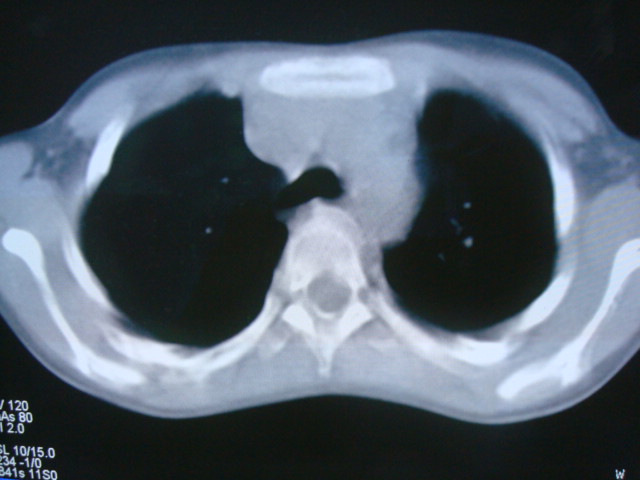

标题: PED0869:男,10岁,肺内多发结节+胸水

男,10岁,左胸痛,发热轻,血象高。后到省级权威医院治疗,病情明显好转,结果几天后公布。老机器,图像质量差,见谅。